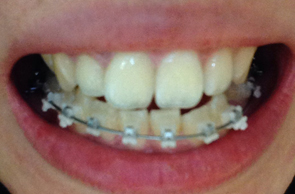

와이어를 장치들 사이에 끼워넣고 탁탁 장치를 맞출때마다 치아가 하나씩 타이트하게 조이는 느낌이 들어왔어요 이때 어느분은 아프다고 느끼실수도 있겠지만 저는 뭔가 딱! 잡아주는 느낌같았어요 뭔가 배에 복대를 했으때의 느낌이랄까 ,,ㅋㅋ

기분좋게 와이어를 갈아끼운후 다음 월치료에 대해 설명해주셨는데

바이트블럭에 익숙해지면서 점차 음식의 난이도가 올라가고 있는 상황들입니다. 쿄쿄 앞으로도 다양한 맛난것들 먹어보려구요 ㅎㅎ